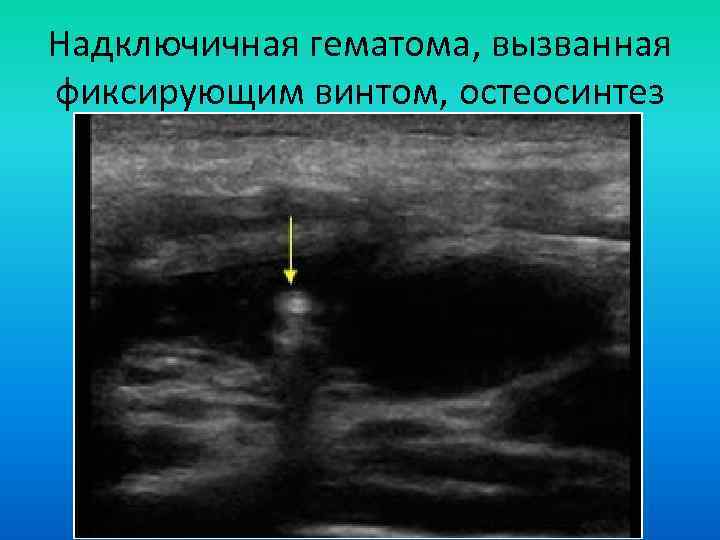

Надключичная гематома, вызванная фиксирующим винтом, остеосинтез Надключичная гематома, вызванная фиксирующим винтом, остеосинтез